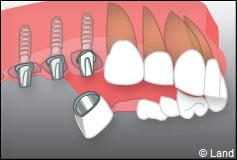

Le chirurgien-dentiste après une anesthésie locale pratique une incision, puis il décolle la gencive pour accéder à l’os alvéolaire.

Ensuite il prépare l’emplacement de l’implant dans l’os en passant plusieurs forets de diamètre croissant. Le forage de l’os se fait à vitesse maîtrisée et lente sous irrigation, pour respecter la structure osseuse et éviter tout échauffement de celle-ci. Le praticien arrête lorsqu’il a obtenu un puits d’un diamètre très légèrement inférieur à l’implant à poser.

L’implant est placé dans l’os le plus souvent par vissage et doit avoir une liaison forte avec l’os. Le praticien replace alors la gencive et pose des points de suture.

Exemple d’un implant unitaire pour remplacer une dent antérieure manquante.